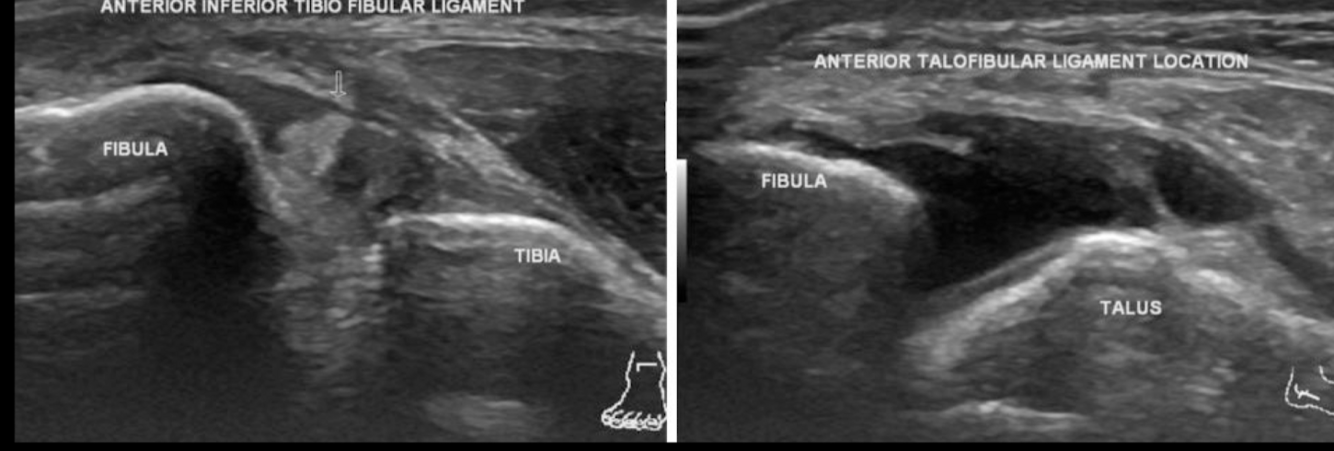

USG esg

A

UTILIDAD LIMITADA

PERMITE EVALUAR ATFL